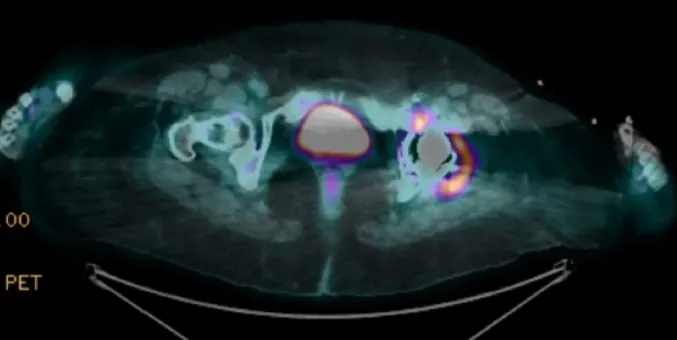

DRC indeterminada ou você esqueceu de fazer o básico? Veja tudo aqui

DRC “indeterminada” raramente é falta de diagnóstico — quase sempre é falta de método. Tempo de evolução, urina bem avaliada, USG renal e história clínica dirigida mudam conduta e evitam erros comuns na prática nefrológica.